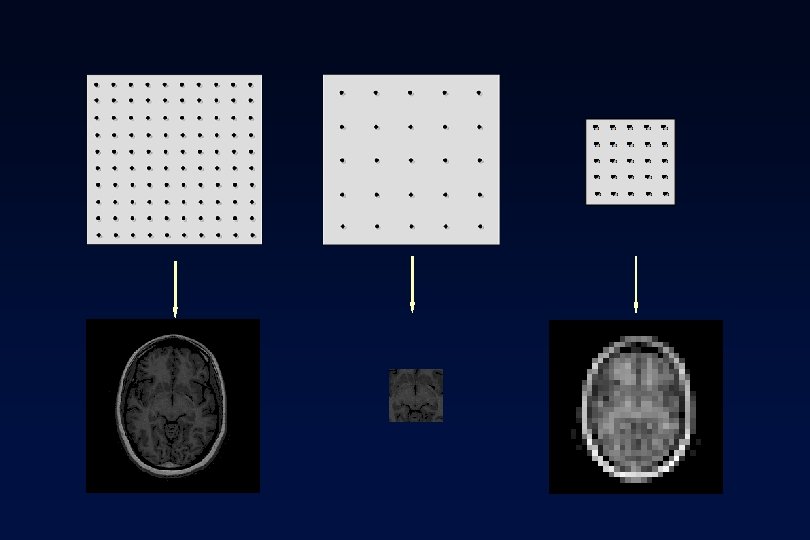

Full Image Full k-space Intensity-Heavy Image Lower k-space Detail-Heavy Image Higher k-space